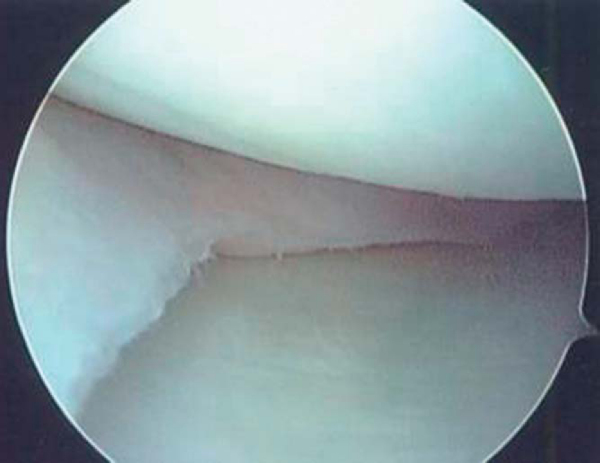

1. Arthroscopic Host Site Preparation

The initial arthroscopic portal should be established on the side opposite the graft, immediately adjacent to the patellar tendon border. This enables passage of the scope through the notch and visualization of the posterior horn attachment. Before the graft-side portal is made, a spinal needle is used to confirm that the portal site is directly in line with the horn attachments. Any obliquity in the skin incision to the horn attachments can cause difficulty in the proper orientation when the bone channel is prepared. Once the portals are made, the meniscal remnant is débrided to approximately a 2-mm vascular rim (Figs. 48-1 and 48-2 [1] [2]). The anterior portion of the meniscus can be addressed after the arthrotomy is made. To ensure proper channel height and alignment, a burr is used to remove the tibial spine to a height that is equal to the level of the tibial plateau articular cartilage and straight in line with the attachment sites. If there is still any difficulty in full visualization of the posterior horn attachment, a limited notchplasty should be performed. Likewise, the entire anterior attachment needs to be seen to be used as a reference for initial placement of the osteotome. Although a tourniquet can be inflated at any time, it is typically not done so until this point. By waiting, it allows confirmation of a vascular rim and conserves tourniquet time. Higher pressure and inflow rates are often needed to limit bleeding during bone channel preparation, which is why the tourniquet may be required at this point in the case.